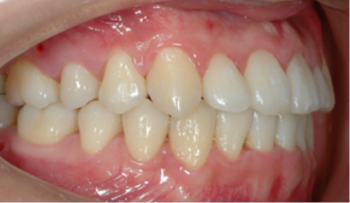

음식을 씹는 기능이 좋아집니다.

칫솔질이 잘 되어 충치나 잇몸 질환이 예방되어 구강 위생이 좋아집니다.

턱뼈의 성장을 조절하여, 주걱턱, 무턱, 비대칭 턱을 해소할 수 있습니다.

얼굴 모양에 좋지 않은 나쁜 습관을 교정해 줌으로써 입 모양이 좋아집니다.

근육 기능이 정상화되면 이갈이, 이 악물기가 줄고 치아 마모도 감소합니다.